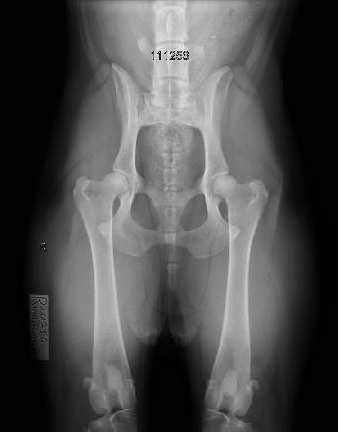

צילומי אגן לוועדת היפ דיספלסיה

בכלבים גזעיים בעלי תעודות יוחסין מבצעים צילומי אגן בהרדמה בדרך כלל מעל גיל שנה. לכל גזע קיים תקנון גידול משלים בו כתוב באיזה גיל ניתן לבצע את הצילום. צילום האגן נשלח לוועדת ההיפ דיספלסיה של ההתאחדות הישראלית לכלבנות המונה שלושה רופאים וטרינרים מומחים ברדיולוגיה.

הכלב מקבל ציון על רמת הפגיעה באגן שלו, הציונים נעים בין A ל E. ציון אגן A לכלב בריא ועל פי חומרת הפגיעה באגן B,C,Dבהתאמה עד לציון E לכלב חולה. בעזרת צילומי האגן נעזרים המגדלים ומבצעים הרבעות מבוקרות על מנת לשפר את הסיכויים לקבל גור בריא שלא יסבול בעתיד מבעיות אגן. צילום האגן נעשה בהרדמה מלאה והוא פעם בחיים ולכן חשוב לבצע את הצילום בצורה הנכונה והמדויקת ביותר.

ד”ר ג’רסי לזר, בשל היותו וטרינר ומגדל של כלבי הקאנה קורסו מבית הגידול Gerassi Corso, פיתח מתקן שעוזר להגיע לשלמות בביצוע הצילום. השלמות במנח הכלב והמהירות בה מגיע ד”ר ג’רסי לזר לצילום המושלם, בעזרת המתקן שלו, למעשה מקצר את משך זמן ההרדמה ובכך בטוח יותר לכלבכם. ד”ר ג’רסי לזר צבר ניסיון רב בתחום צילומי האגן בכלבנות הגזעית ומבצע צילומי אגן לכל גזעי הכלבים משנת 2000. לד”ר ג’רסי לזר רנטגן דיגיטאלי מודרני וחדשני, ובנוסף מעניק יעוץ ועזרה חינם בכל ההליך מול וועדת ההיפ דיספלסיה של ההתאחדות הישראלית לכלבנות.